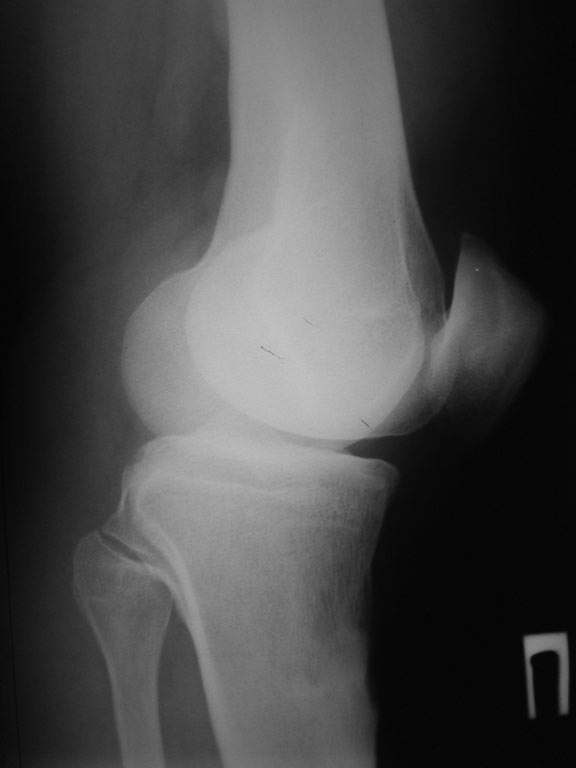

Пациент наконец то объявился вновь, и мы смогли выполнить новые снимки как лежа, так и в нагрузке.

Не смотря на плохое качество снимка и недостаточный размер кассеты, а также наружную ротацию коленного сустава, снимок показывает отсутствие сгибательной контрактуры.

Мой совет : остеотомоя большеберцовой кости тотчас дистальнее прикрепления собственной связки надколенника, малоберцовой кости в средней или на границе нижней и средней трети голени, аппарат Илизарова в компановке, подобной в моей презентации.

Величина коррекции равная величине переразгибания в коленном суставе.